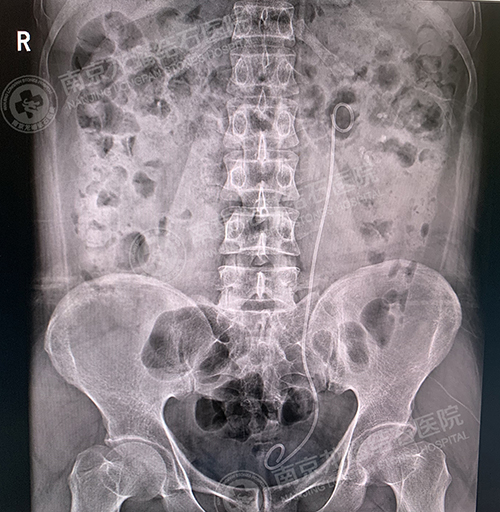

术前

术后

2020年5月9日12时35分,泌尿外科二病区主任梁和建成功为呼先生实施了经尿道左输尿管镜钬激光碎取石术,成功将左输尿管下段数枚不规则黄褐色结石击碎取出。最大约1.3cm。